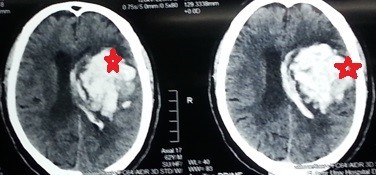

نزيف بالنصف الكروي الايسر بالمخ ممتد لبطينات المخ

hemorrhage in the left hemisphere of the brain extending to the ventricles of the brain

A case of a patient in the sixth decade of life suffering from chronic high blood pressure who had a sudden deterioration in the degree of consciousness with hemispheric weakness. By doing a CT scan on the brain, he found severe bleeding in the left hemisphere of the brain, extending to the ventricles of the brain. A successful microscopic surgery was performed to empty the bleeding, after which the patient returned to his normal state.